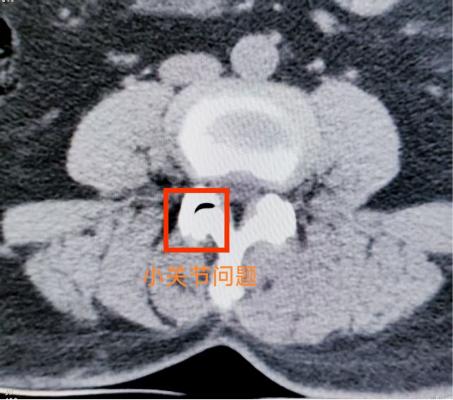

腰椎小關節(jié)增生紊亂:腰椎后方兩側成對的小關節(jié),負責穩(wěn)定脊柱并引導活動。它們如同門上的合頁,一旦因勞損、退變導致軟骨磨損、骨質增生,或發(fā)生微小錯位,就會引發(fā)深層、定位模糊的腰痛。疼痛常在腰部扭轉、后伸時加劇,有時晨起僵硬感明顯。